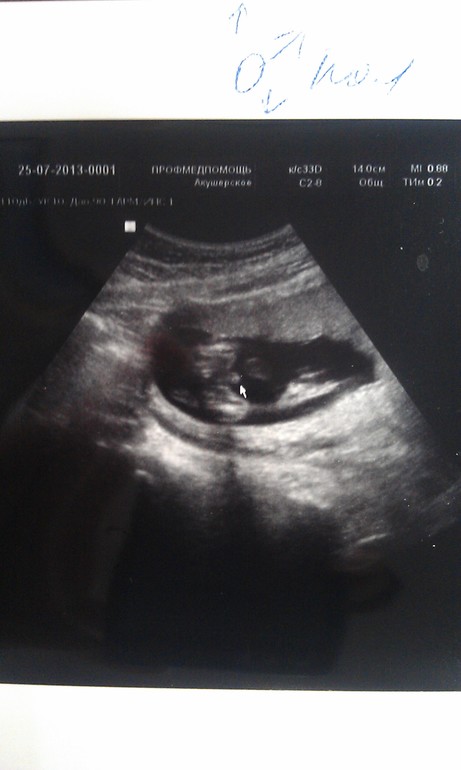

25 июля - УЗИ, у нас мальчик 100%!!!!!))))) наш папа безумно рад!!! И с его стороны и с моей одни девочки))) все ждут наследника))) по УЗИ мы опережаем развитие почти на неделю....))) наши шевелюшки все отчетливее))) вес малыша 225 гр.